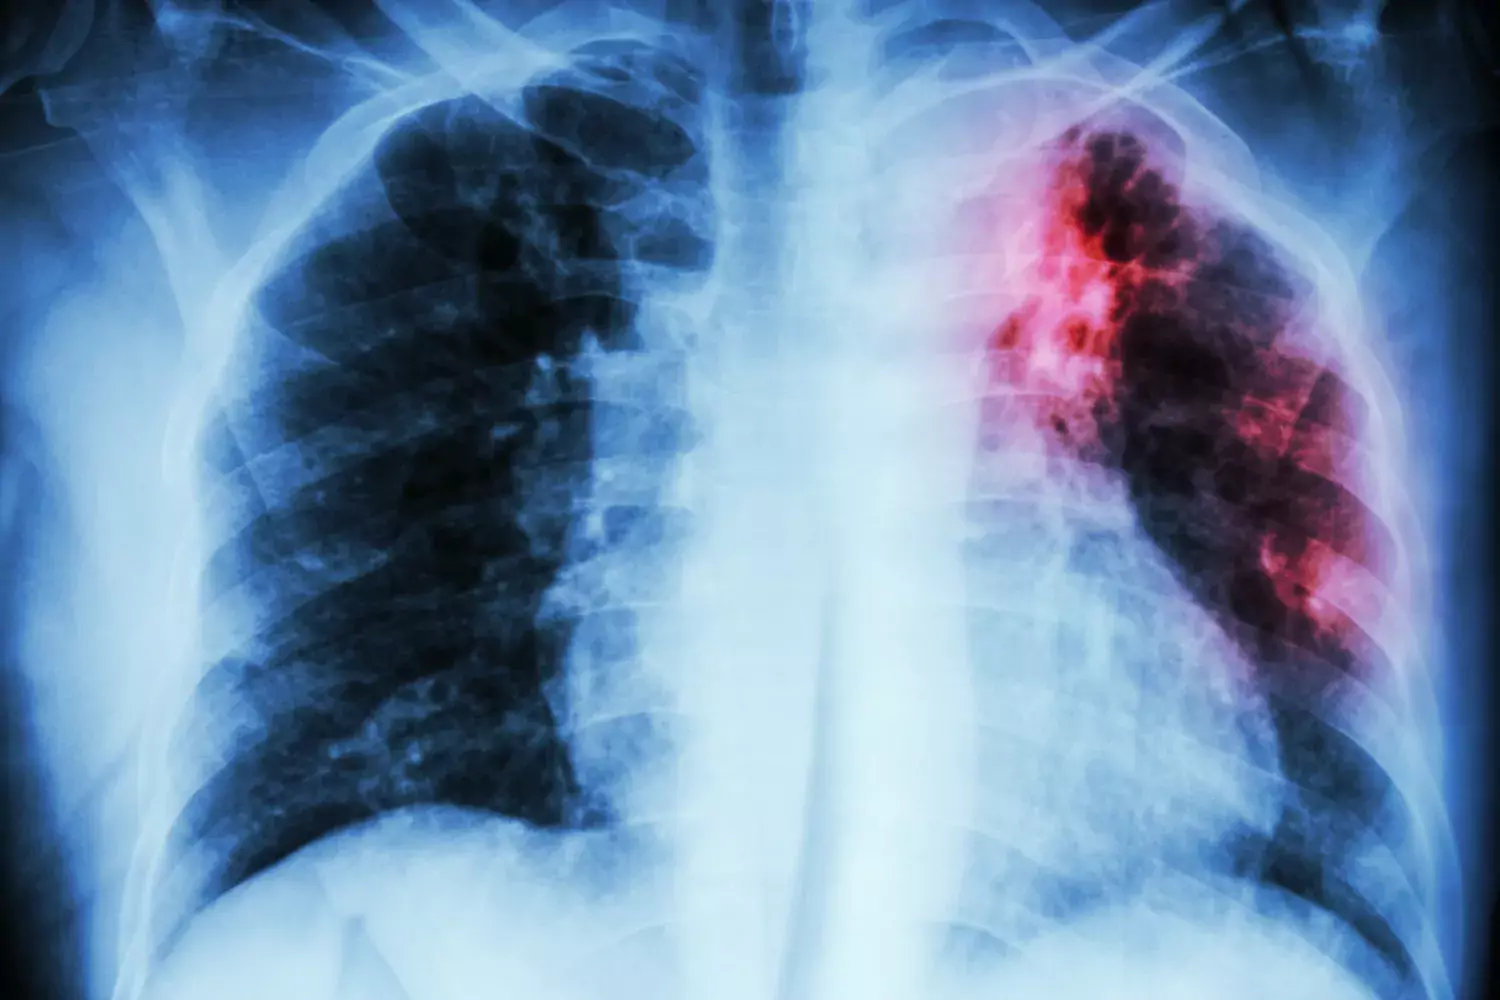

Tuberculosis, or TB, is an infectious disease caused by bacteria from the mycobacterium family, mainly Mycobacterium tuberculosis. The most common form of the disease attacks the lungs, but it can also take other forms and affect the lymphatic system, spine, brain or other bodily organs. Pulmonary tuberculosis is highly contagious as it is transmitted when infected people cough or sneeze, releasing tiny aerosol droplets with bacteria into the air.